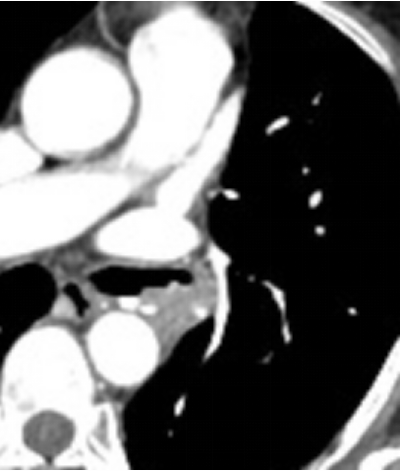

胸部CT增强扫描左上叶开口后靠近背部位置“结节”中的血供丰富,CT值>100。建议患者行支气管动脉栓塞术。

图片